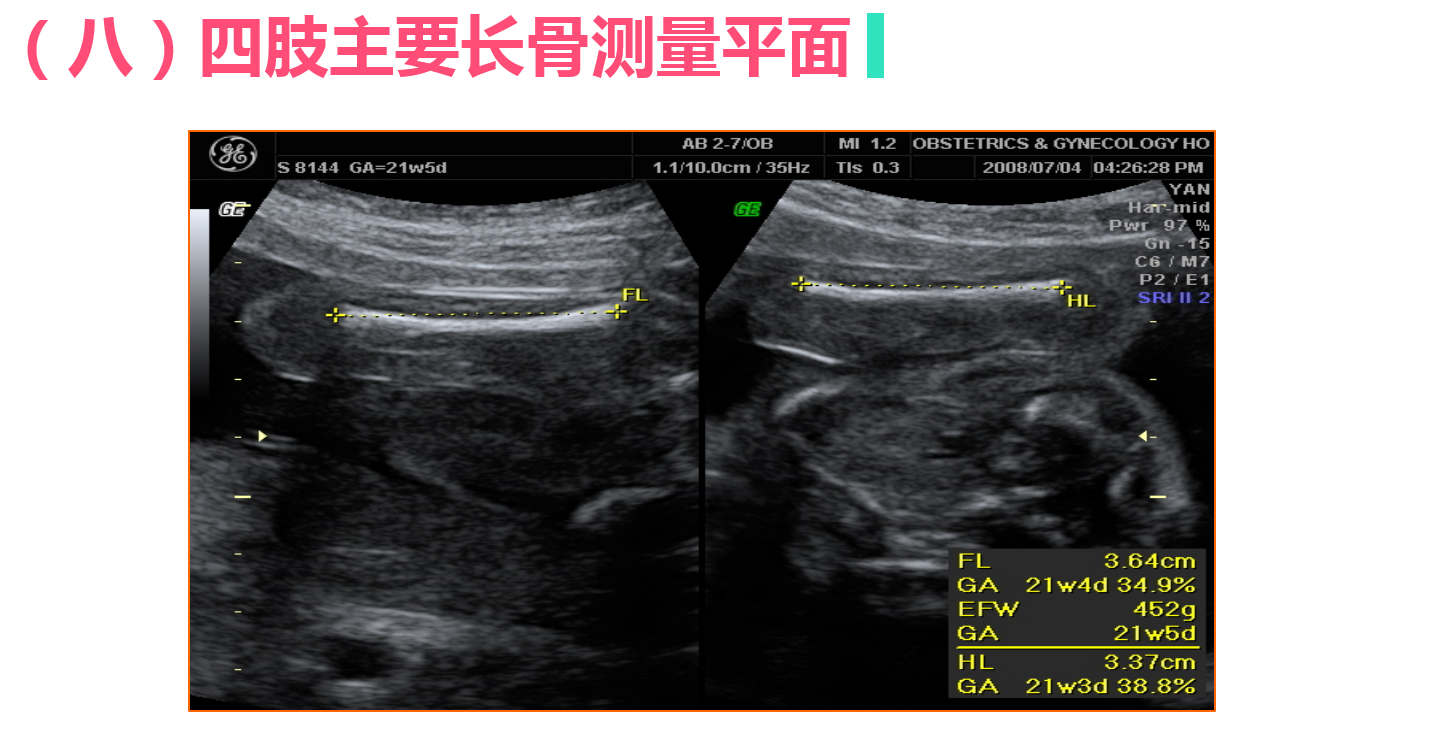

• 4.3 正常中晚期妊娠声像图

正常中晚期妊娠声像图